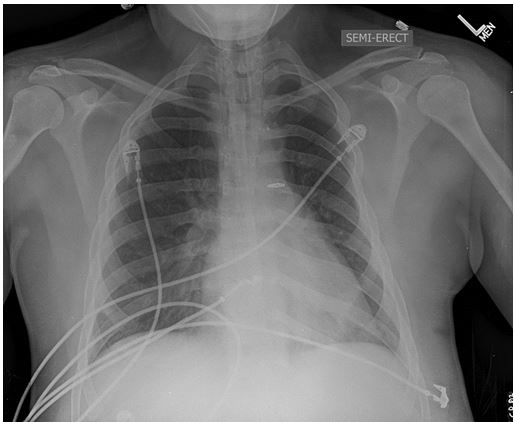

Figure 1. Chest Radiograph showing generally clear lung fields without obvious focal airspace disease.